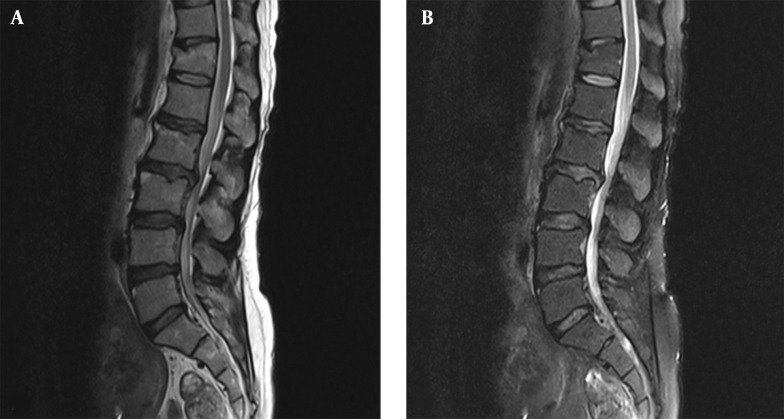

Case presentation: We report the successful use of spinal anesthesia (SA), ESPB, and magnesium sulfate in a high-risk patient with systemic sclerosis and pulmonary fibrosis undergoing laminectomy. A multimodal approach was selected due to the patient's underlying condition. This strategy minimized respiratory complications associated with general anesthesia while providing effective surgical anesthesia and postoperative pain control without opioid-related complications.